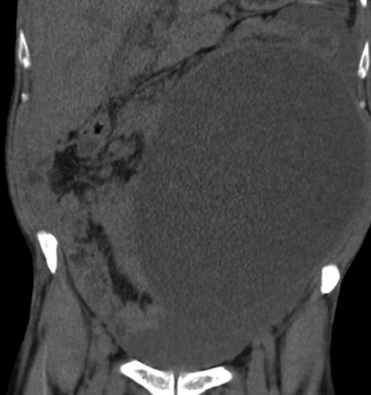

Imágenes y Cirugía

Camila Valenzuela Labra, Raúl Valenzuela Labra, Jaime Cruz Fuentes, Matías Orellana Pérez, Marcelo Villarroel Soto, Hernán Valenzuela Valenzuela